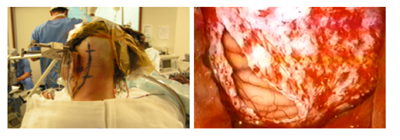

The classic retrosigmoid approach (Figure 1) presents the ventral part of the pons as a limitation; the extension of this approach is an alternative, with removal of a part of the mastoid bone and the temporal bone and a 50% increase of the angle of vision, which allows the ventral approach with lower cerebellar traction.22 Hauck EF et al.23 described 9 cases using pre sigmoid approach (Figure 2) with access to the lateral part of the pons, between the facial and trigeminal nerves, perpendicularly towards the brainstem.

Figure 1 A: Skin markin the retrosigmoid approach in a semi-seated position.

B: Dural opening adjacent to the left sigmoid sinus.